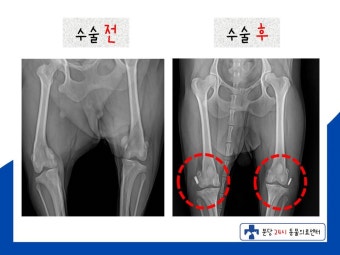

치료법은 상태에 따라 다릅니다.

- 1~2단계: 보존적 치료 (운동 제한, 체중 조절, 물리치료)

- 3~4단계: 수술적 치료 (무릎뼈 위치 조정, 인대 강화 등)

9. 수술은 꼭 필요한가요?

모든 경우에 수술이 필요한 건 아니지만, 탈구가 자주 반복되거나 통증이 심한 경우에는 수술이 권장됩니다.

특히 3단계 이상일 경우 방치하면 관절염이나 골절 등 2차 문제가 생길 수 있어요.